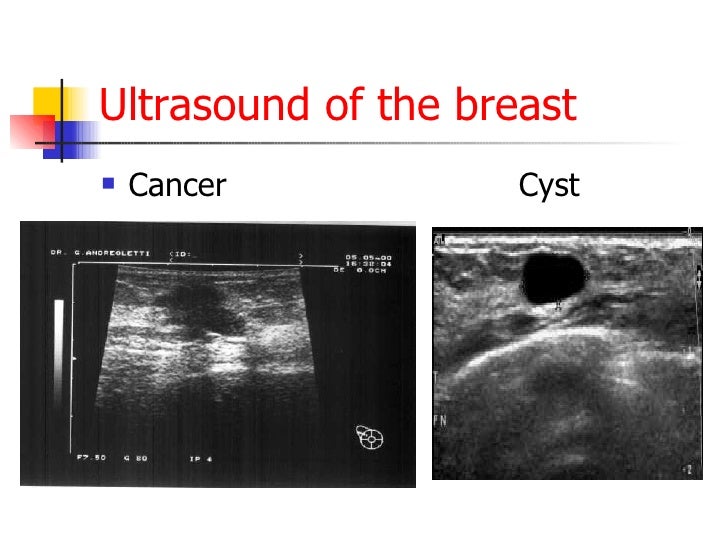

Mammogram images: Normal, abnormal, and breast cancer

breast cancer on ultrasound looks like Mammogram images: Normal, abnormal, and breast cancer